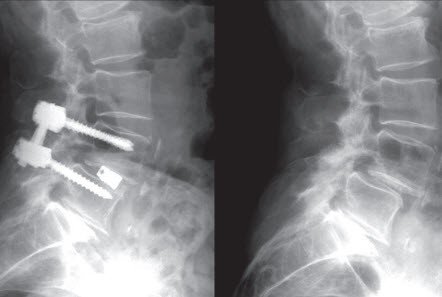

Wenn der Patient neben Beinbeschwerden zusätzlich starke Kreuzschmerzen hat oder ein Wirbel verschoben ist, wird nach der Erweiterung des Spinalkanals auch öfters eine Versteifung durchgeführt. In der einfachsten Form können zwei Wirbel durch eine Gelenkverschraubung fixiert werden. Oft ist das aufwändigere Verfahren mit dem Einsetzen von Schrauben in die Bogenwurzeln und eventuell zusätzlicher vorderer Abstützung zur Wirbelversteifung erforderlich. In jedem Fall wird Knochen oder Knochenersatz-Material für eine dauerhafte Stabilität zusätzlich verwendet.

Die Erweiterung des Spinalkanals mit allfälliger Versteifung erfolgt über einen dorsalen (rückenseitigen) Zugang mit vertikalem Hautschnitt in der Mitte des Kreuzes.